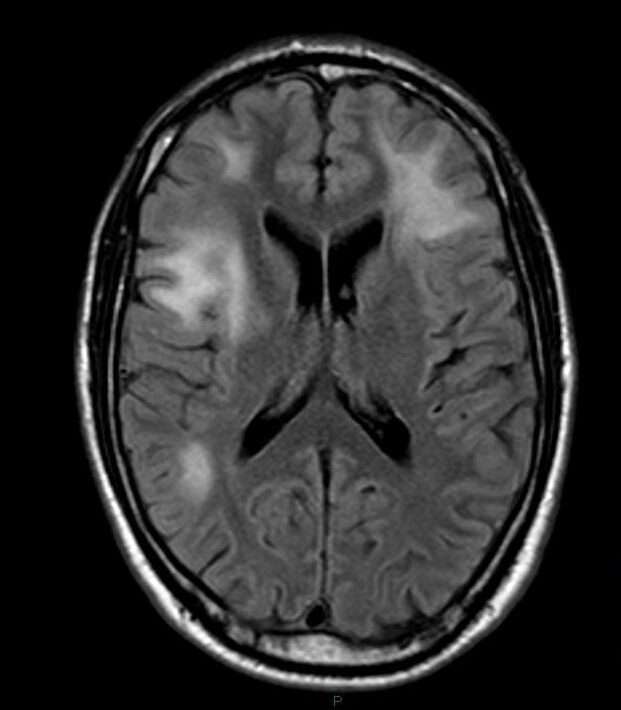

En cuanto a los estudios de imagen, la resonancia magnética cerebral es el pilar fundamental para la evaluación estructural en sospecha de leucoencefalopatía multifocal progresiva. Los hallazgos característicos incluyen áreas multifocales de desmielinización en la sustancia blanca cerebral, generalmente sin efecto de masa ni realce con contraste. Estas lesiones suelen ser bilaterales, aunque pueden presentarse de forma asimétrica, y afectan con frecuencia las fibras en U subcorticales. No obstante, estas alteraciones pueden ser difíciles de distinguir de las observadas en el síndrome inflamatorio de reconstitución inmune, especialmente en pacientes con inmunosupresión que inician recuperación inmunológica, como aquellos con tratamiento antirretroviral en el contexto de infección por el virus de la inmunodeficiencia humana.

Aunque los hallazgos por resonancia magnética son de gran utilidad, deben interpretarse en conjunto con los datos clínicos y de laboratorio, dado que los informes de casos muestran una considerable variabilidad en las imágenes, y la enfermedad puede manifestarse de formas atípicas. Por tanto, el diagnóstico de leucoencefalopatía multifocal progresiva debe basarse en un enfoque integral y multidisciplinario que contemple todas las dimensiones del paciente y de la enfermedad.